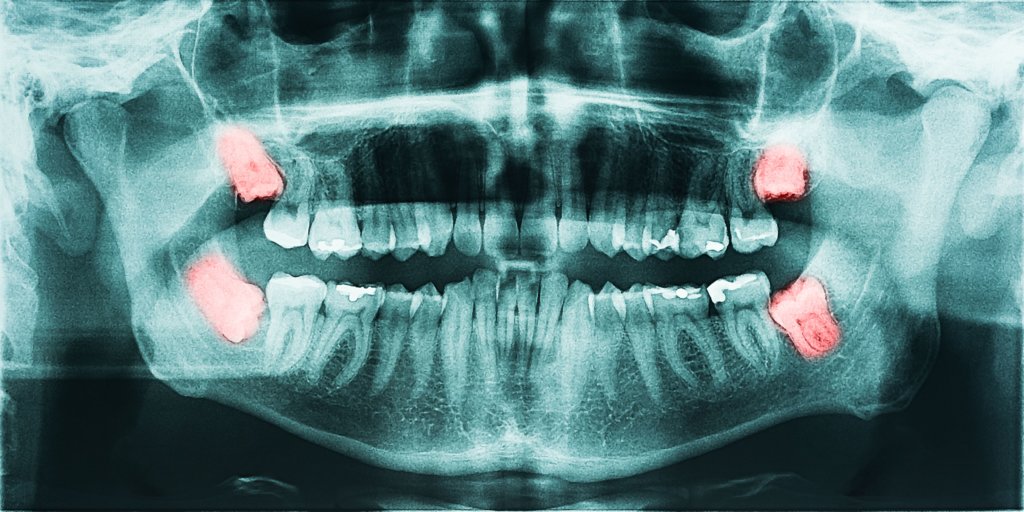

此外基於清潔不易的理由,智齒多半也都是以拔掉來處理;最後是較少見的囊腫病灶,也會迫使牙醫師選擇以拔掉牙齒來作治療。

牙齒矯正治療中的患者,由於空間不足,在矯正醫師的要求下,需將四顆智齒拔除。

以本案例來說,除了本身智齒就埋得深,加上矯正器與骨釘擋住了拔牙器械施力的位置,因此處理的口腔顎面外科醫師得細心閃躲、避免弄掉了矯正器或弄鬆骨釘,在口腔最深處作出大小適中的創口,將牙齒切成多塊,分批拿出來。

本案例下顎第三大臼齒因天生位置不良、不易清潔,常常導致第二大臼齒後側嚴重蛀牙。

在第二大臼齒還有救的情況下,就必須小心謹慎地將智齒移除,並且不傷害到前頭已經結構受損的第二大臼齒。

許多人以為這是很容易的事,事實上施力方向不正確的話,常常導致第二大臼齒牙冠無預警的碎裂,這可就不容易處理了。

前文有提到,大臼齒通常都有兩個以上的牙根,若在比較沒有注意的情況下,可能會遺漏了牙根而不自知。

少數智齒牙冠周圍的萎縮釉上皮會產生變異,形成所謂的含牙囊腫,造成骨質缺損,甚至感染而引發更大的問題。

處理該囊腫通常會⼀併將患齒也移除,而由於手術範圍較⼤大、容易影響到下顎齒槽神經與臨牙,因此該類治療自然也是口腔顎面外科醫師的範圍,透過嫻熟的技術,方能在不損及正常組織的情形下將囊腫與牙齒都拿乾淨,給患者最好的癒後。